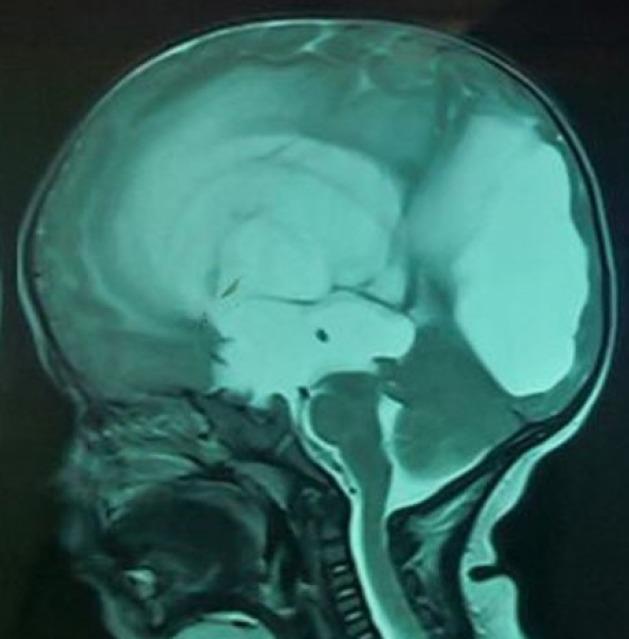

Endoscopic third ventriculostomy (ETV) has now become an accepted mode of hydrocephalus treatment in children. Varying degrees of success for the procedure have been reported depending on the type and etiology of hydrocephalus, age of the patient and certain technical parameters. Review of these factors for predictability of success, complications and validation of success score is presented.

内镜下第三脑室造瘘术(ETV)现已成为治疗儿童脑积水的一种公认方式。根据脑积水的类型和病因、患者年龄以及某些技术参数,该手术已报道有不同程度的成功率。本文对这些因素进行综述,以探讨其对手术成功率的预测性、并发症以及成功评分的验证情况。